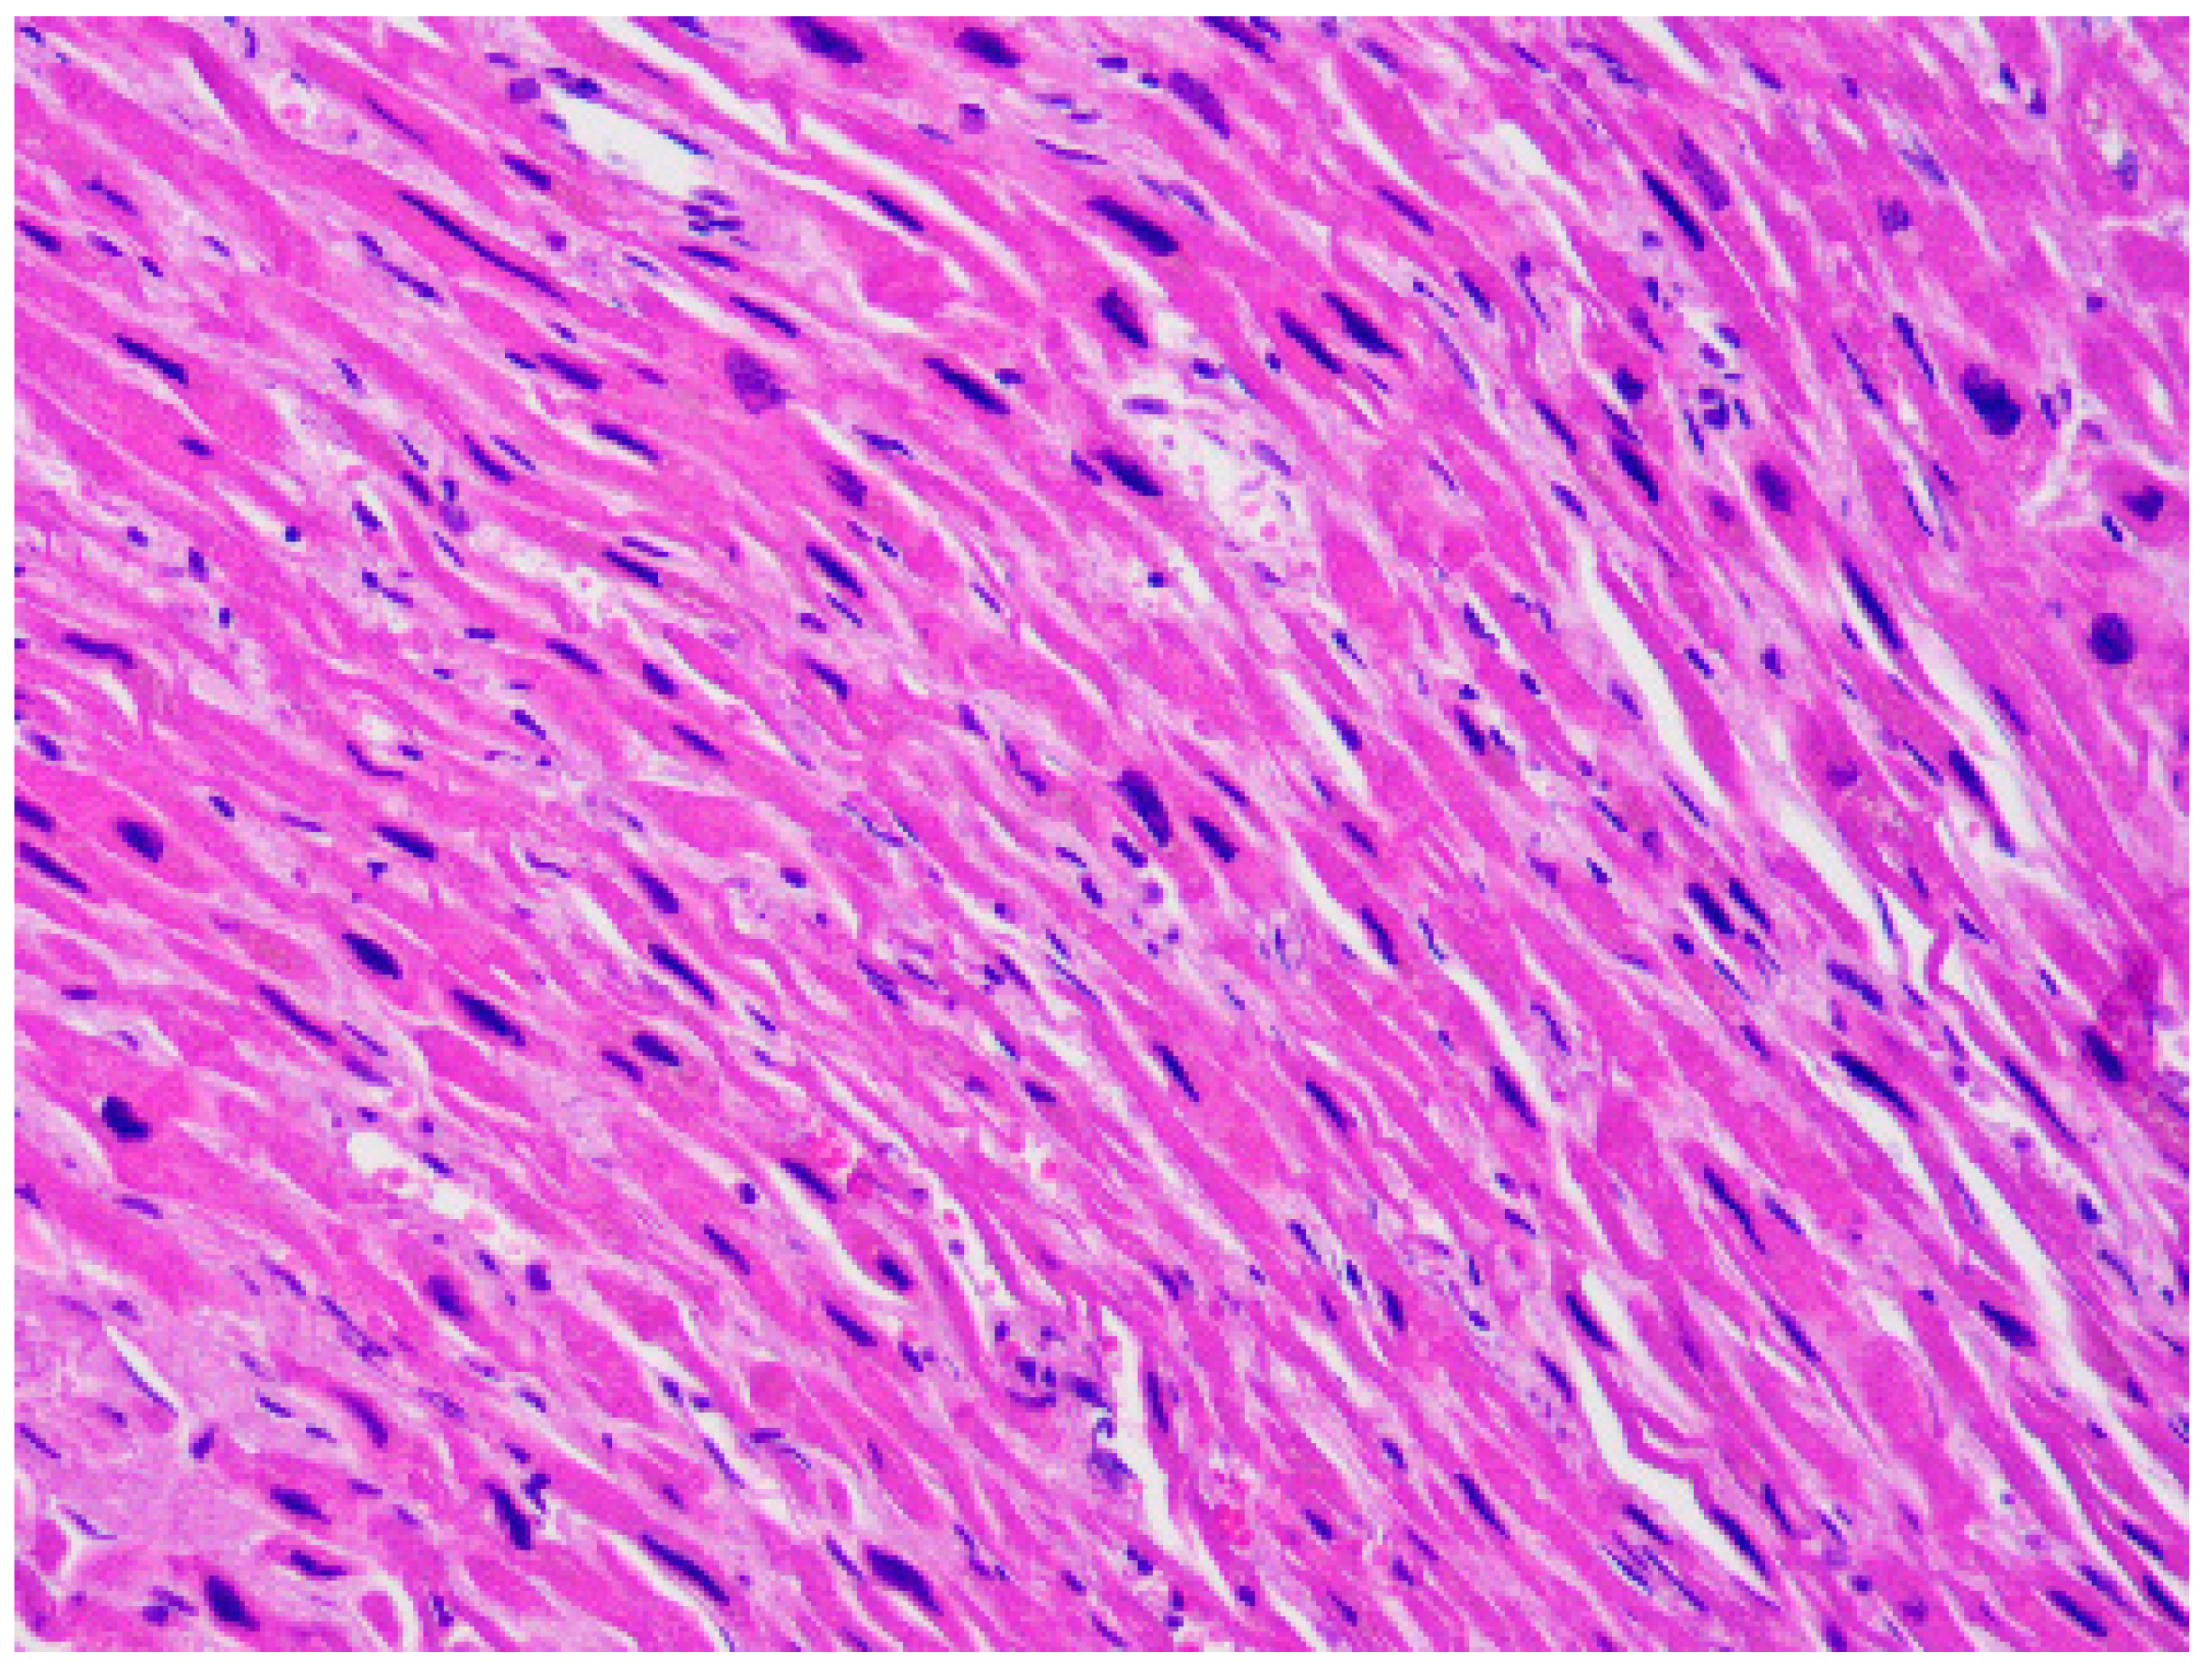

| Typical histopathological features | Myocytes hypertrophy, disarray, thickened intramural arterioles with luminal narrowing, myocardial fibrosis [102,103] | Fibrofatty replacement of the ventricular myocardium with a subepicardial-mid-mural or transmural distribution [54] | Replacement fibrosis, interstitial fibrosis, atrophied and/or hypertrophied cardiomyocytes, nuclear pleomorphism [82] |